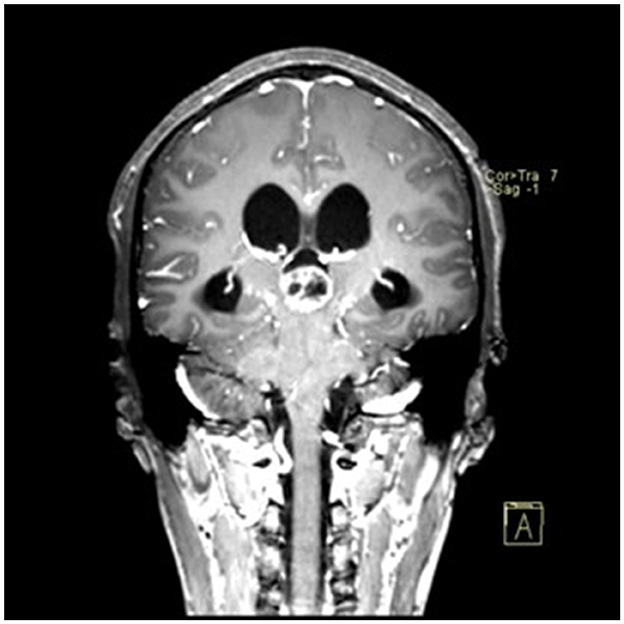

A 22-year-old male presented with intermittent dizziness and headache lasting for 2 weeks. MRI at admission revealed a cystic mass in the pineal region, accompanied by supratentorial hydrocephalus (Figures 3–5). No surgical contraindications were identified. After discussion with the patient's family, neuroendoscopic resection was performed via the Transfrontal-Transventricular-Transforaminal Approach. Intraoperatively, a 20 × 20 mm soft, well-vascularized tumor was found obstructing the cerebral aqueduct. The lesion had well-defined margins and was carefully dissected from surrounding adhesions, preserving adjacent veins and brain tissue. Macroscopic total resection was achieved en bloc (Figures 6–8). Postoperative day 1 MRI confirmed complete tumor removal and resolution of hydrocephalus (Figures 9–11). Postoperatively, no complications were observed. However, due to personal reasons, the patient was discharged on postoperative day 11. Histopathology confirmed a mixed germinoma. No recurrence or surgery-related complications were noted during follow-up.

Figure 5

Preoperative contrast-enhanced MRI (coronal view) showing the pineal region tumor.